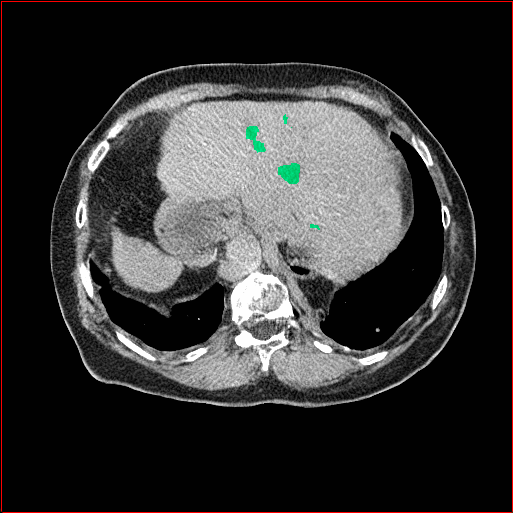

MAISI-v2 Controlnet qualitative Results:

Figure 5 shows qualitative results for MAISI-v2 Controlnet on 5 types of tumors.

Liver Tumor

0.75×0.75×0.50.75\times 0.75\times 0.5

mm

512×512×768512\times 512\times 768

Figure 5: MAISI-v2 segmentation-guided results for five types of tumors. We show results for different voxel spacing and volume size to demonstrate the flexibility of MAISI-v2. Different Hounsfield Unit window is used to better show the contrast between tumor and normal tissues.